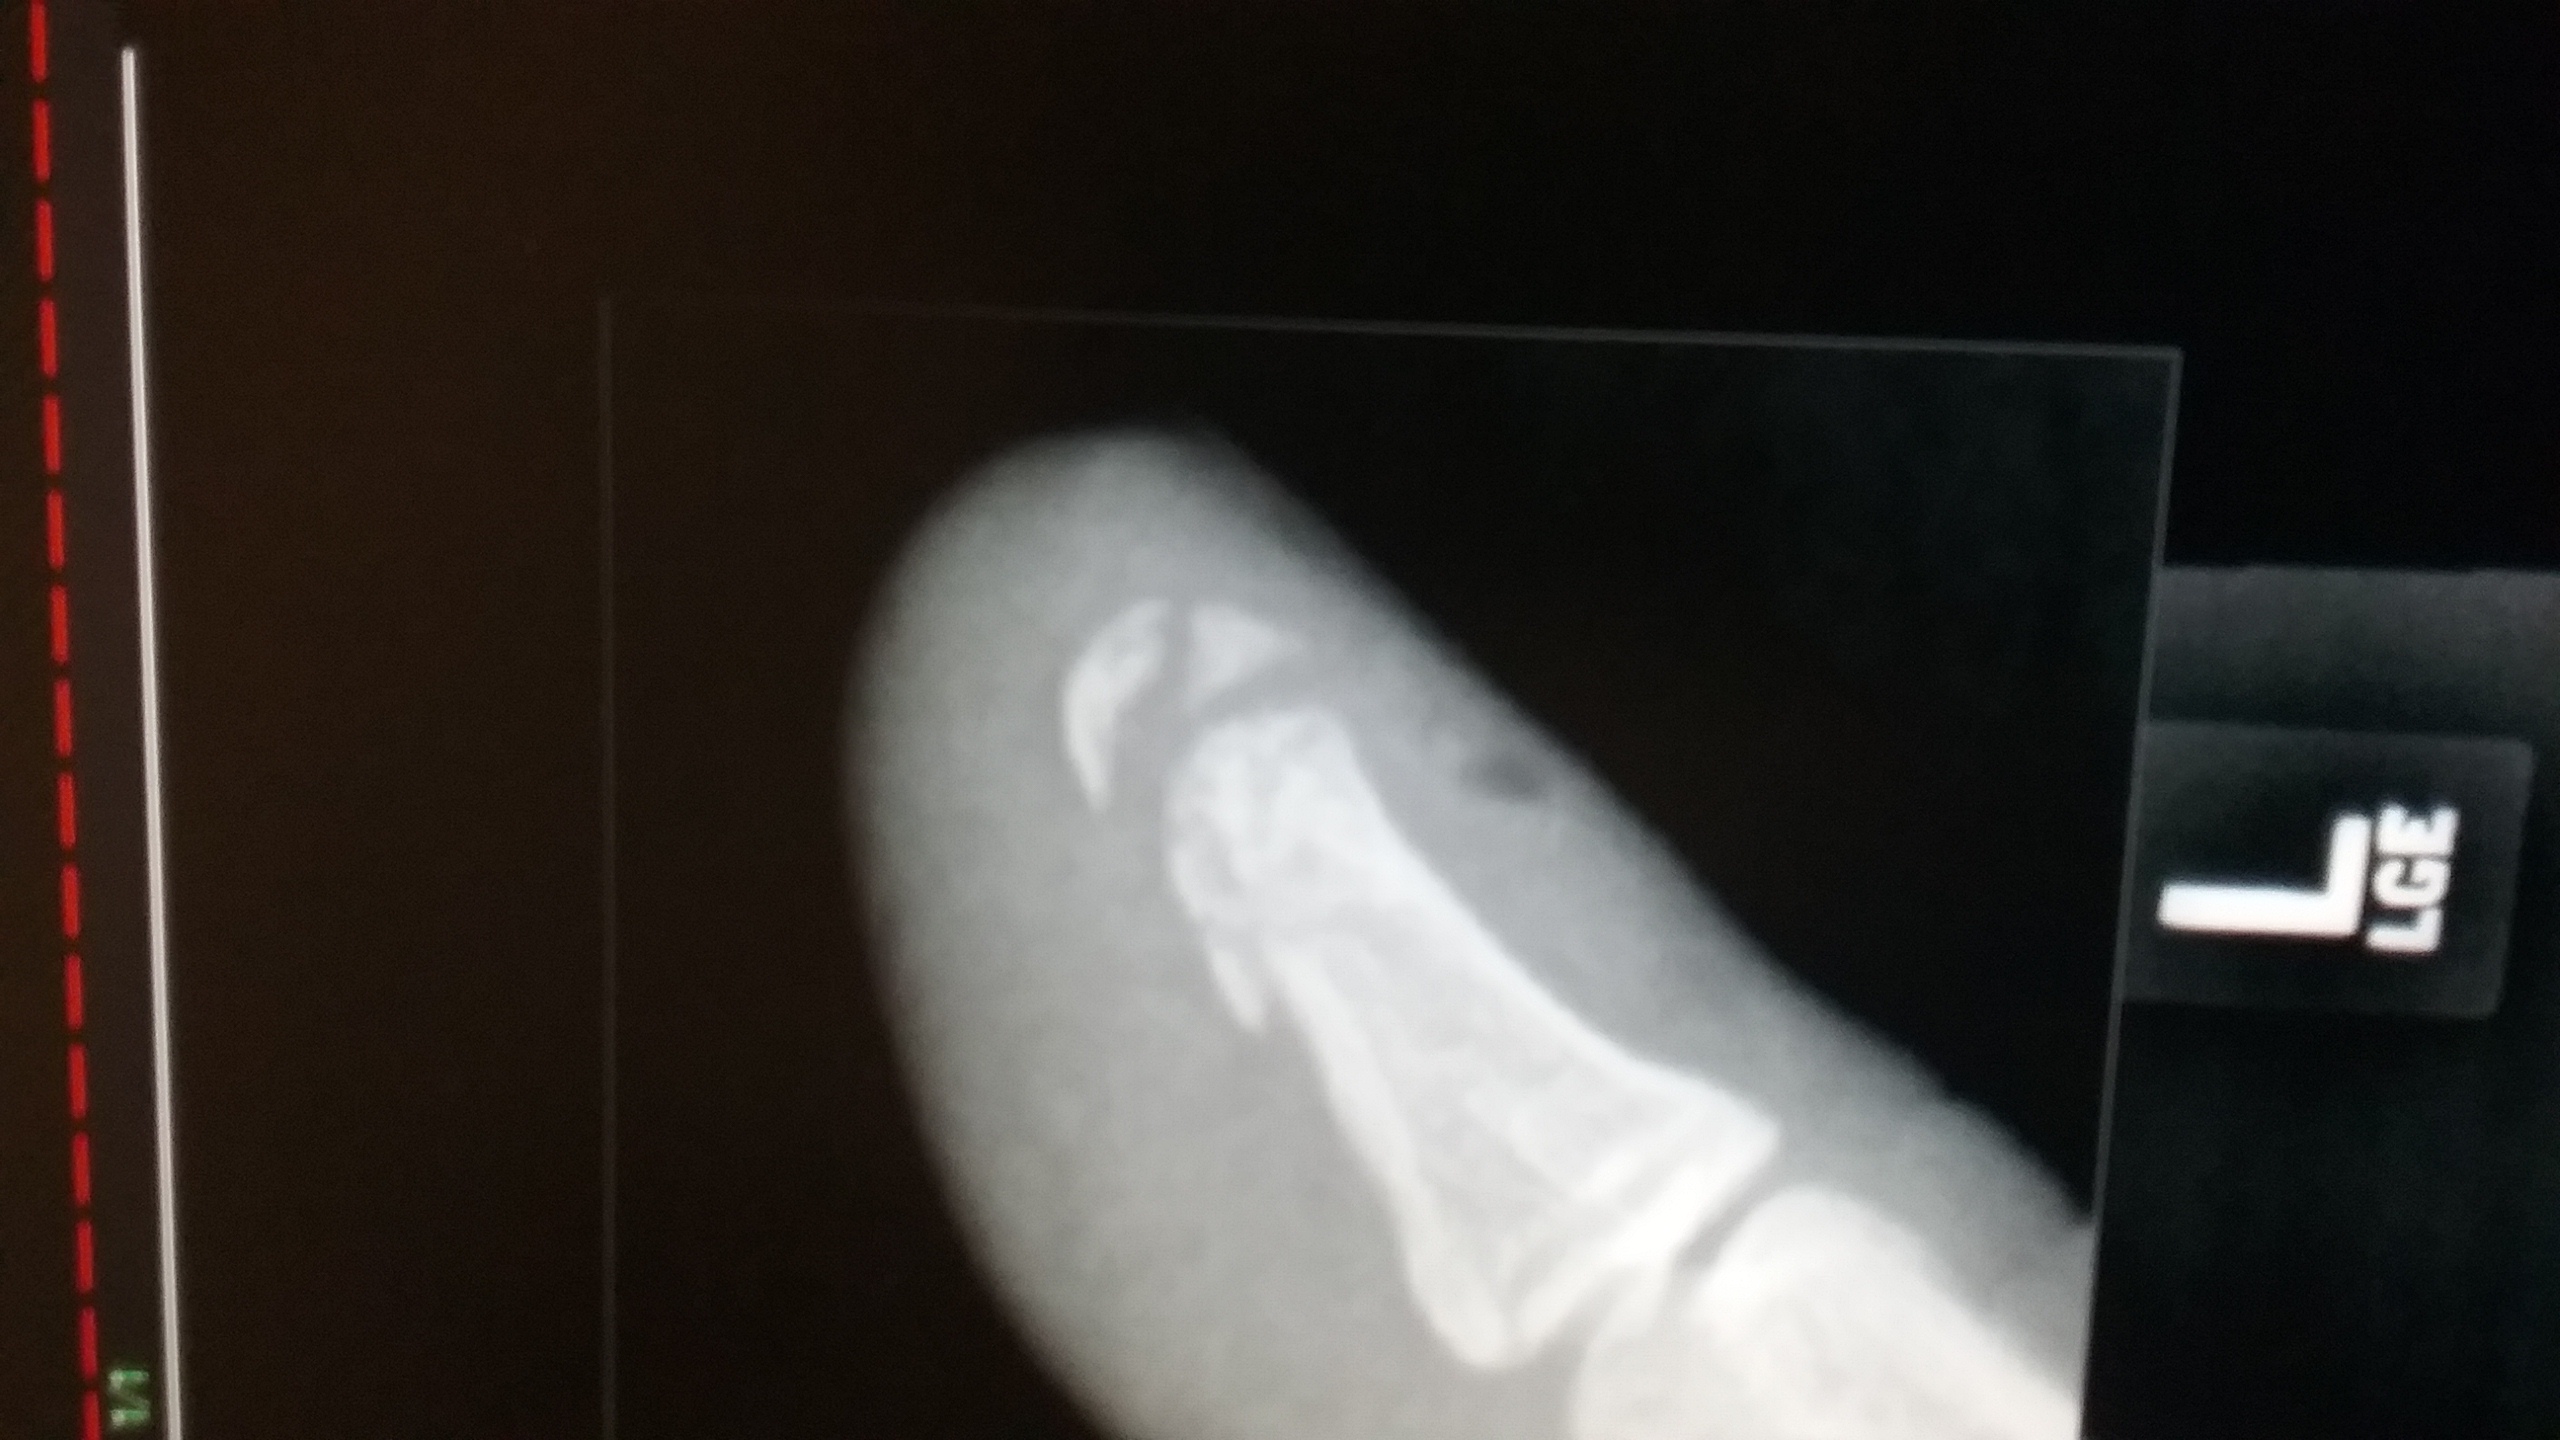

The thumb wasn't healing very quickly and i keep aggrivating it. So i had some x rays done....4 chunks of bone in the tip of my thumb. 1489797037768.jpg